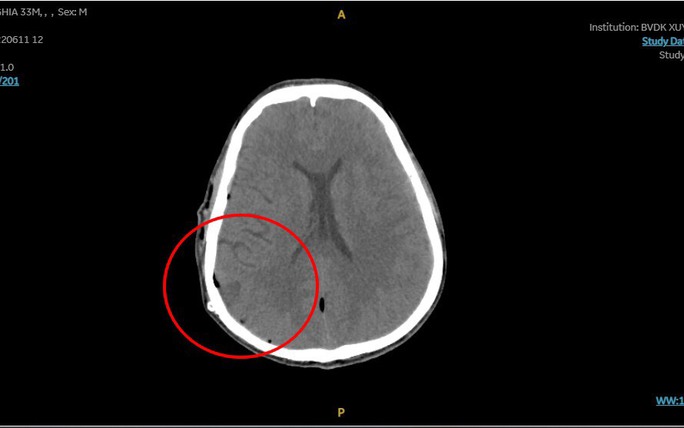

Kết quả chụp CT cho thấy sọ của bệnh nhân có đường nứt nhẹ, xuất huyết não do đứt một mạch máu nhỏ vì chấn thương. Bệnh nhân được đưa vào phòng mổ để cầm máu, hút máu tụ khoảng 150 ml.